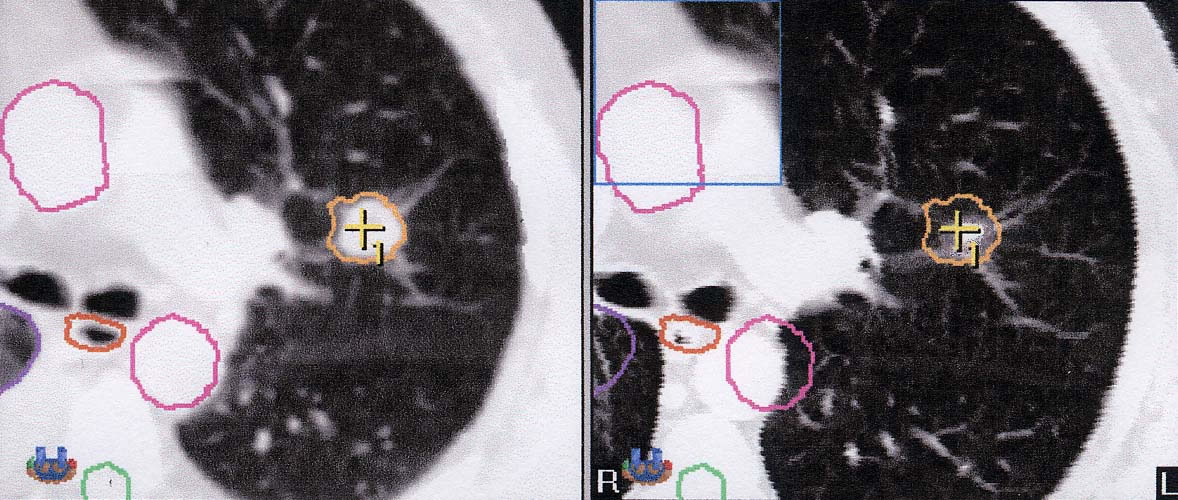

Stereotaxie-Bestrahlung bei Bronchialkarzinom: Behandlungsergebnis